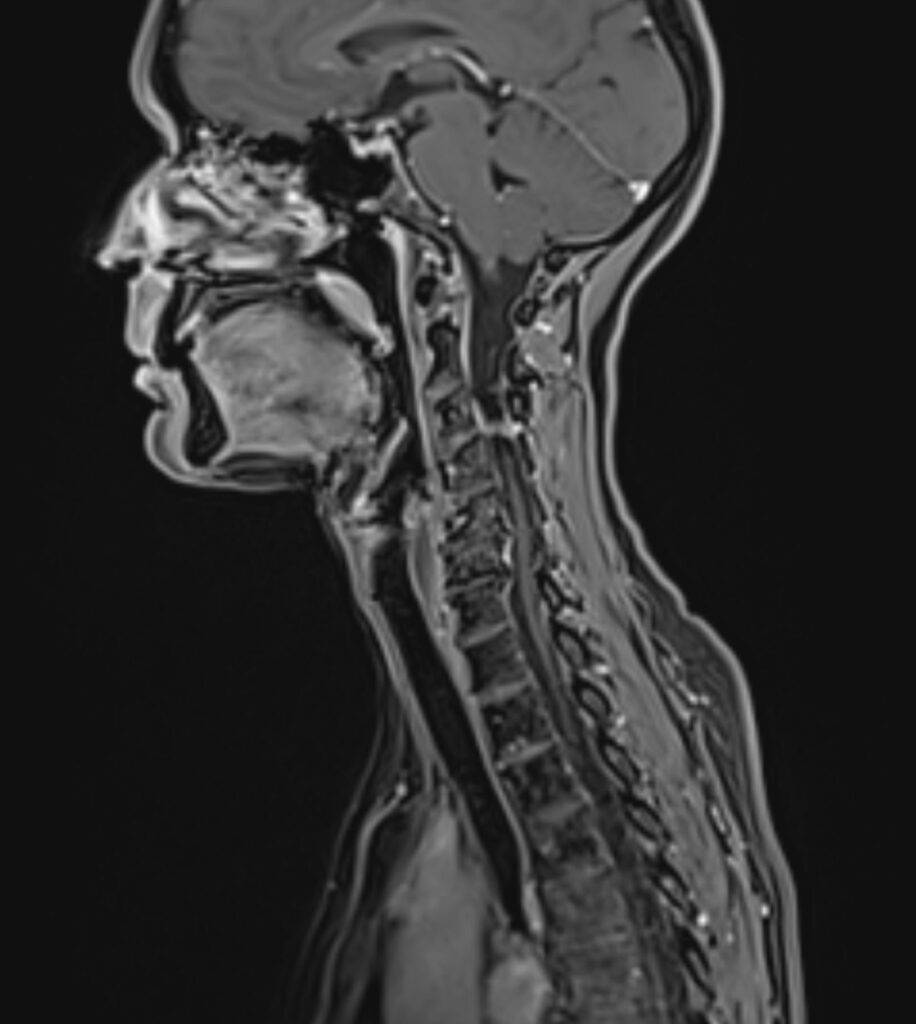

MRT Kopf – was sieht man?

Eine Kopf MRT liefert Ärzte und Radiologen detaillierte Bilder. Zu sehen sind das Gehirn, Schädelknochen, Blutgefäße und anderer umgebende Gewebe im Kopfbereich.

„MRT Kopf“ bezieht sich allgemein auf die Untersuchung des gesamten Kopfbereichs, einschließlich Gehirn, Schädel und umliegender Strukturen. „MRT Schädel“ sowie „MRT Gehirn“ beziehen sich auf dieselbe Untersuchung. Unterschieden wird im untersuchenden Bereich: Gehirn, Schädelknochen, Nase und Nasennebenhöhlen, Ohr oder Kiefer.